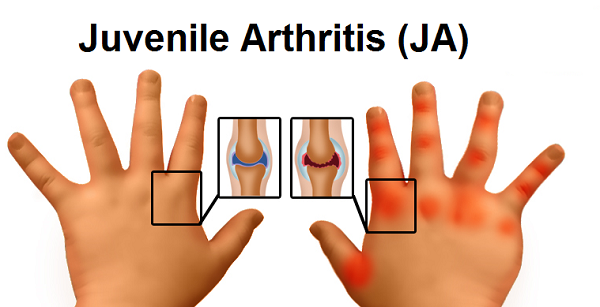

However, it may come up as a shocking revelation for many to know, that arthritis could affect children below the age of 16 years or even lesser!

Juvenile Idiopathic Arthritis:

Rheumatoid arthritis in children is known as juvenile rheumatoid or juvenile idiopathic arthritis. Causes and symptoms are similar to rheumatoid disease explained earlier. However, some of the symptoms commonly observed in children have been listed below.

Symptoms:

- Children with this ailment may develop vision troubles. Delayed diagnosis and treatment may lead to permanent vision problems or blindness.

- Children who have learned to walk may again start crawling when affected with this arthritis

- Limping is a common and visible symptom of this disease

- Fever and flu like symptoms

- Painful and swollen joints

- Retarded growth and slow rate of development